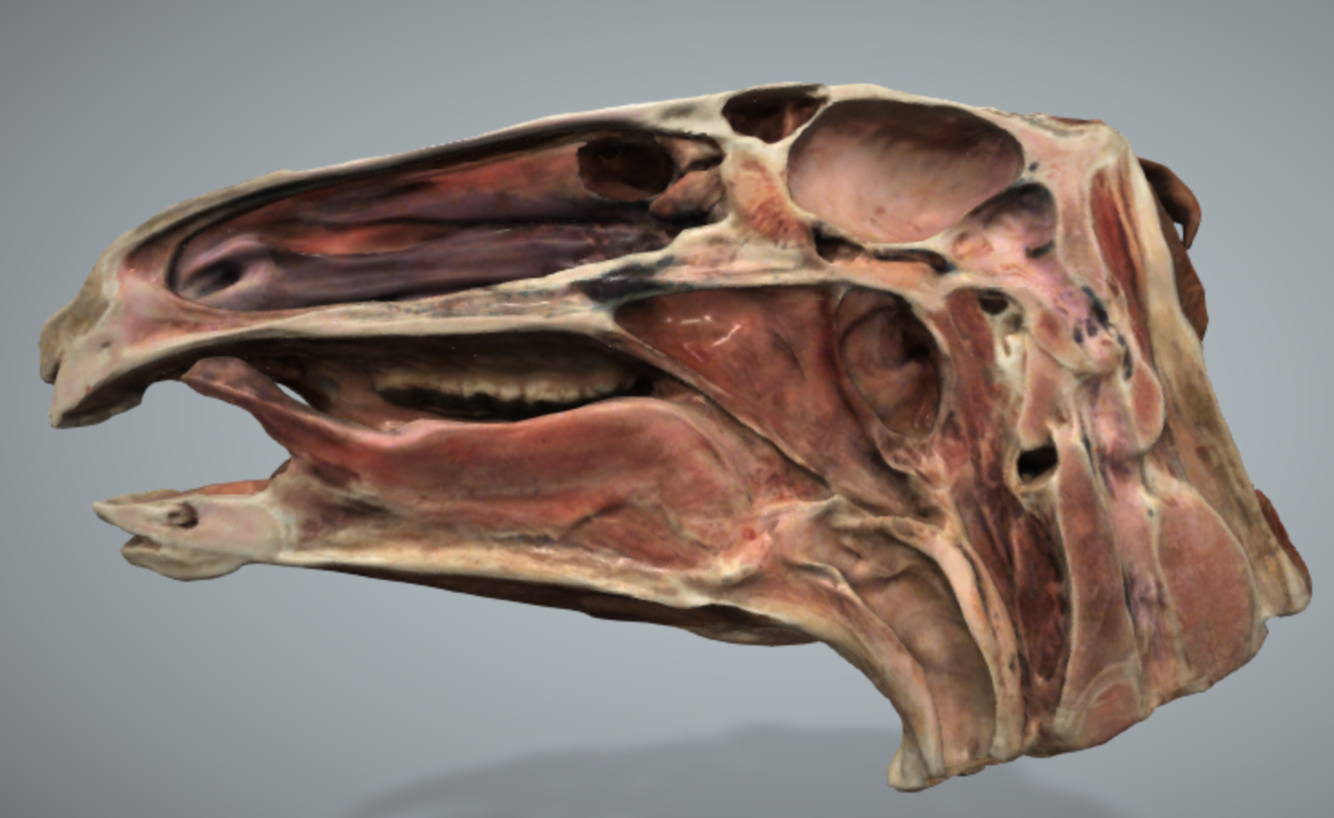

The sinuses have been impregnated with silver to highlight their extent and boundaries. Note the extent of the frontal and maxillary sinuses and their relationship to each other. The boney septum which divides the maxillary sinus into a rostral and caudal compartment is also highlighted. Identify 1-4.

1 =infraorbital canal

2 = frontal sinus

3= septum separating caudal maxillary sinus from rostral compartment

4= rostral maxillary sinus

Which cheek teeth lie within the rostral maxillary sinus and which lie within the caudal maxillary sinus?

¾ and 5/6

The rostral and caudal maxillary sinuses increase in size with age as the reserve crowns of the cheek teeth move down as the teeth wear.